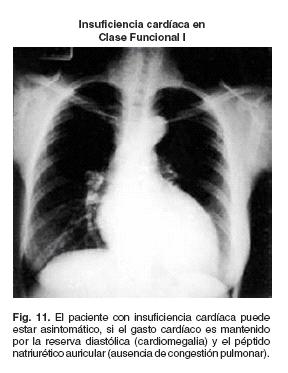

1) Factor natriurético auricular

Cuando se utiliza el mecanismo de FrankStarling, el aumento del estrés diastólico consecutivo al aumento de volumen diastólico tiene dos efectos importantes: por un lado, aumenta la presión diastólica ventricular y por el otro normaliza el gasto cardíaco (Tabla I). El aumento de la presión diastólica intraventricular trae consigo a su vez, aumento de la presión de la auricula izquierda y ello condiciona aumento del estrés de la pared auricular, lo cual en el mecanismo gatillo para la secreción de péptido natriurético, el cual como su nombre lo indica, es realmente un diurético interno que al promover la diuresis evita la congestión venosa pulmonar y sistémica, con la peculiar característica de bloquear la secreción de Renina.42 Las consecuencias finales son:

a) Aumento de gasto cardíaco

b) Sin congestión venosa (Fig. 11)

Como se mencionó previamente un paciente con insuficiencia cardíaca puede estar completamente asintomático a pesar de utilizar su mecanismo de FrankStarling que normaliza al gasto cardíaco (Tabla I), cuando el factor natriurético auricular es capaz de evitar el aumento exagerado del volumen y la presión diastólica intraventricular, y con ello la congestión pulmonar42 (Insuficiencia cardíaca compensada asintomática) pero, si el mecanismo de FrankStarling no logra mantener un gasto cardíaco adecuado, se activa el mecanismo adrenérgico y el sistema RAA con lo que se logra normalizar el gasto cardíaco pero las consecuencias del efecto de estas neurohormonas producen taquicardia y la retención hídrica y en estas condiciones, la compensación (normalización del gasto cardíaco) produce síntomas de congestión venosa sistémica y pulmonar o sea la connotación de insuficiencia cardíaca compensada no significa que el paciente se encuentre asintomático, sino que se encuentra vivo; ello significa que realmente los síntomas que presenta un paciente con insuficiencia cardíaca, son aquéllos producidos por los mecanismos compensadores y no directamente por la falla contráctil39 y como ya se mencionó previamente, cuando los mecanismos compensadores, no logran normalizar el gasto cardíaco aparece hipoperfusión tisular y las manifestaciones de insuficiencia cardíaca: Obnubilación mental, oliguria, palidez, diaforesis, que preceden a la muerte.39 Así el término insuficiencia cardíaca descompensada no se refiere al paciente que tiene síntomas (disnea, fatiga, edema, etc.), sino al paciente en el que sus mecanismos compensadores no han logrado normalizar el gasto cardíaco y la perfusión tisular (choque cardiogénico).39 Cuando el paciente tiene síntomas de insuficiencia cardíaca (disnea, edemas, fatiga, etc.) pero mantiene una perfusión tisular adecuada, (clase funcional II, III o IV) es más adecuado denominar al cuadro como insuficiencia cardíaca sintomática (Fig. 15) ya que en estas condiciones los mecanismos adaptativos mantienen el gasto cardíaco y la perfusión tisular: Insuficiencia cardíaca compensada sintomática.

La clase funcional por sí misma no define el tipo de enfermedad cardíaca, así como tampoco, el tipo de afectación anatómica o funcional del corazón. Esta aclaración es pertinente porque en algunos estudios la clase funcional es la que define la presencia de insuficiencia cardíaca y su gravedad sin haber cuantificado necesariamente, la fracción de expulsión53 o bien este parámetro se calificó en > 50% o < 50% solamente por apreciación visual y en forma retrospectiva.54 En la figura 16, se demuestra cómo en pacientes con infarto agudo de miocardio pueden encontrarse en insuficiencia cardíaca (fracción de expulsión < de 50%) y aun muy grave (fracción de expulsión < de 20%) y encontrarse asintomáticos (clase funcional I) y por otro lado, pacientes con disnea (congestión pulmonar) que se encuentra en clase funcional II, tienen una fracción de expulsión normal (> 50%). En los primeros el factor natriurético auricular puede ser el responsable de la ausencia de síntomas42 (Fig. 11) y en el segundo grupo, la disfunción diastólica es la responsable de la congestión pulmonar (vide infra) y no la insuficiencia cardíaca.

En la figura 17A se presenta la radiografía del tórax de un paciente con insuficiencia cardíaca importante (fracción de expulsión 32%) en clase funcional I (asintomático), en quien los mecanismos de Starling (Tabla I) y el factor natriurético43 permite la compensación (gasto cardíaco normal) y la ausencia de congestión venosa pulmonar (Insuficiencia cardíaca compensada asintomática). En la figura 17B un paciente con insuficiencia cardíaca (fracción de expulsión 28%) con disnea de pequeños esfuerzos (clase funcional III) sintomático, por importante hipertensión venocapilar, la compensación se ha hecho a través de la activación del eje RAA, el cual ha normalizado el gasto cardíaco pero a costa del uso excesivo del mecanismo de FrankStarling (Insuficiencia cardíaca compensada sintomática).